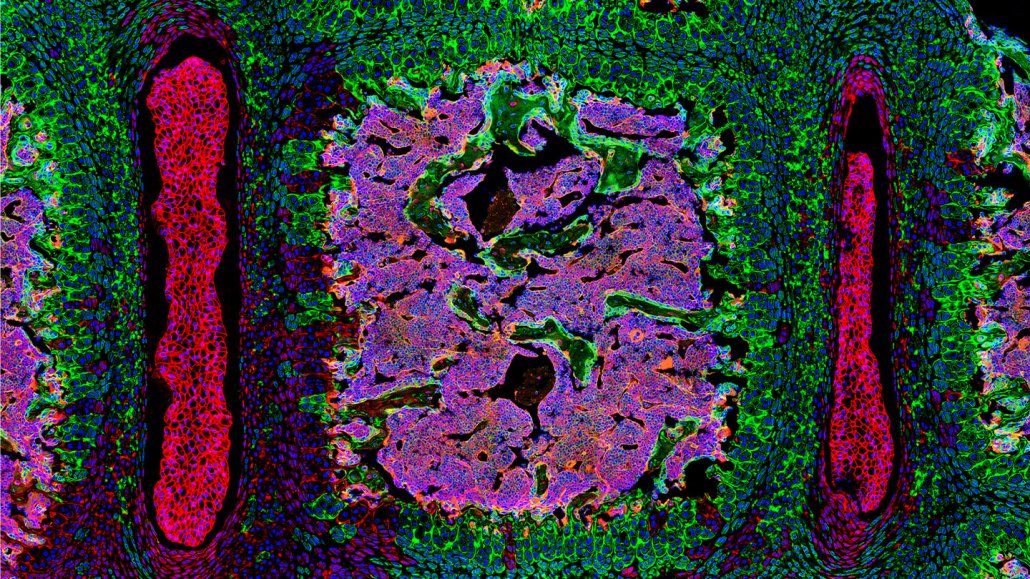

An image of newly discovered stem cells shown in green.

Scientists have discovered a new type of stem cell that forms spinal tissue (in mice, these stem cells and the cells they produce are shown in green).

J. Sun et al./Nature 2023